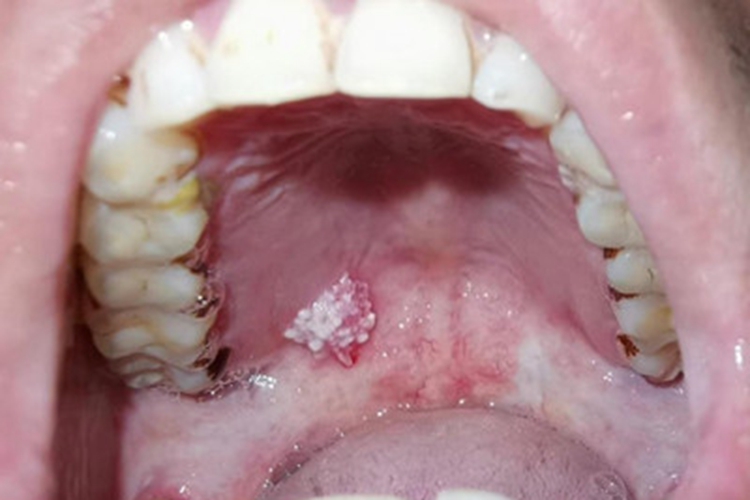

口腔尖锐湿疣可累及口腔位置,表现为单个或多个无痛性的疣状结节,有蒂或无蒂,可逐渐增大或融合,形成菜花状、乳头状赘生物,与边缘界限清楚,颜色呈肉色或苍白色,患者可有异物感。